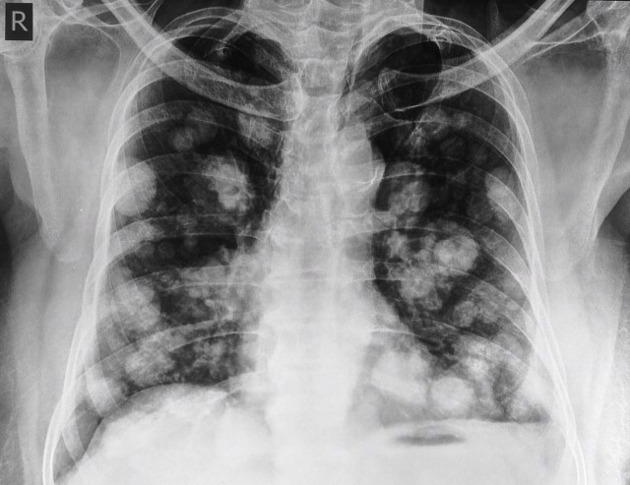

English: Lung metastasis refers to cancer that has spread to the lungs from another part of the body. This secondary cancer occurs when cancer cells break away from the primary tumor and travel through the bloodstream or lymphatic system to the lungs.

- Imaging: Chest X-ray, CT scan, and PET scan to visualize lung metastasis.

English: Lung metastasis is a common occurrence in advanced cancer stages. The incidence varies depending on the type of primary cancer, with lung metastasis occurring in up to 30-55% of patients with metastatic disease.